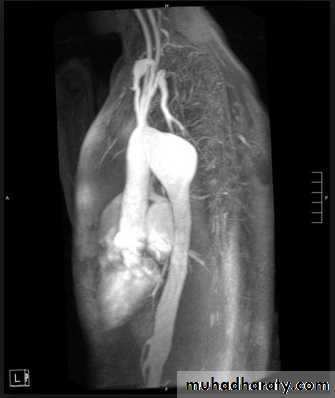

The plain film shows features which are typical for spinal tuberculous disease.

There is an extensive paraspinal soft-tissue mass.

Detail in the underlying spine is poor but there is early crowding of ribs posteriorly, indicating early vertebral collapse.

(B) Coronal MR image of the thoracic spine demonstrates destruction of the intervertebral disc at the point where the paraspinal widening is maximal and this change is associated with alteration of signal from the vertebrae.